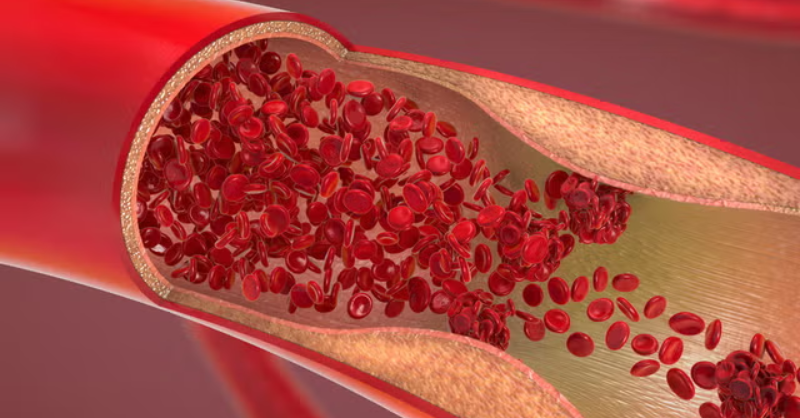

Signs of a Blood Clot That You Should Never Ignore, According to Doctors

Blood clots are part of the body’s natural defense system, sealing off injuries to stop bleeding. But sometimes, clots form without any injury—and that’s where the problems begin....